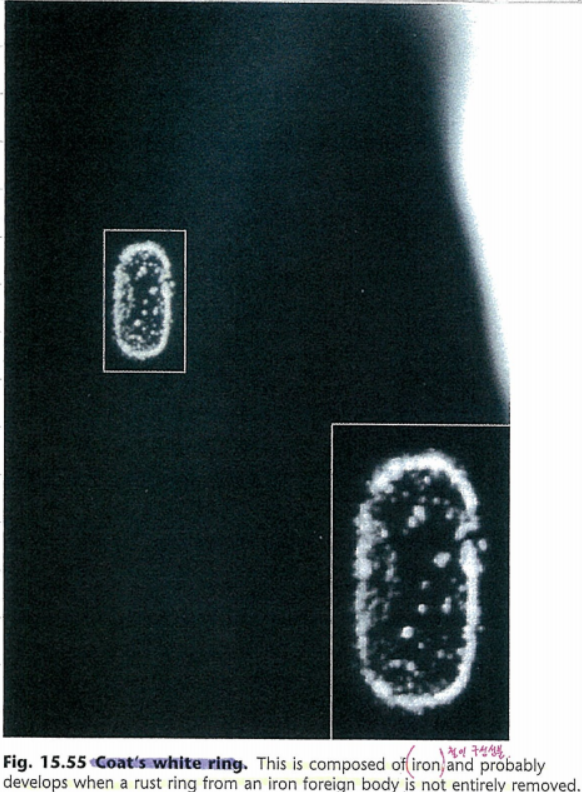

안과의사 코우츠 Coats 에 의해 기술된 질환으로,

각막 하부에 위치하는 타원형 혹은 불완전한 공모양 혹은

백색의 점들이 융합하는 지름 1mm이하의 고리모양의 백색의 원을 의미합니다.

보우만층과 기질의 표층에서 고리모양으로 백색의 점들이 침착된 모양인데,

철이 구성성분으로, 아마도 철분성의 이물질이 남고 난뒤, 제거하였으나,

완벽하게 제거되지 않으면서, 부식성 녹 고리 rust ring 녹이 남으면서 그것들이 환형으로 침착된 것으로 생각됩니다.

크기는 보통 1mm 이하로 백색환은 기질 전부에서 관찰됩니다.